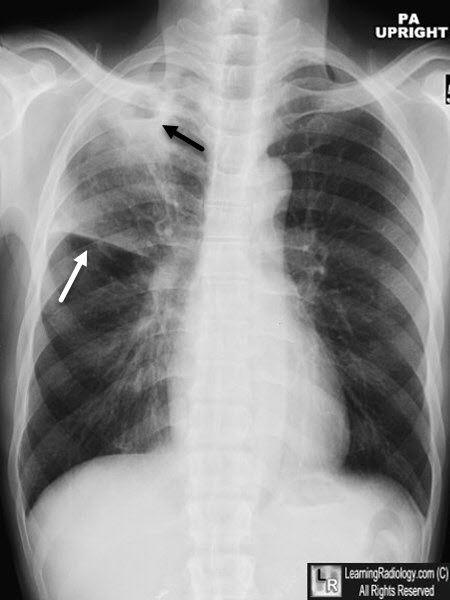

一位28岁的女性,单位体检,做了个胸片,提示左上肺有个阴影,建议进一步检查。

后来又做了个CT,提示炎性病灶,不排除肺结核。

- 胸部影像学检查显示与活动性肺结核相符的病变。

- 胸部影像学显示与活动性肺结核相符的病变,患者有咳嗽、咳痰、咯血等肺结核的可疑症状。

- 胸部影像学检查显示与活动性肺结核相符的病变,PPT试验强阳性或γ-干扰素释放试验(又叫T-SPOT)阳性。

- 胸部影像学检查显示与活动性肺结核相符的病变,经过诊断性抗菌治疗两周无效,或随访检查可以排除其他原因导致的肺部疾病者。